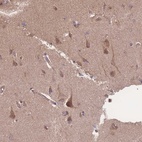

Immunohistochemical staining of human cerebral cortex shows cytoplasmic positivity in neuronal cells.